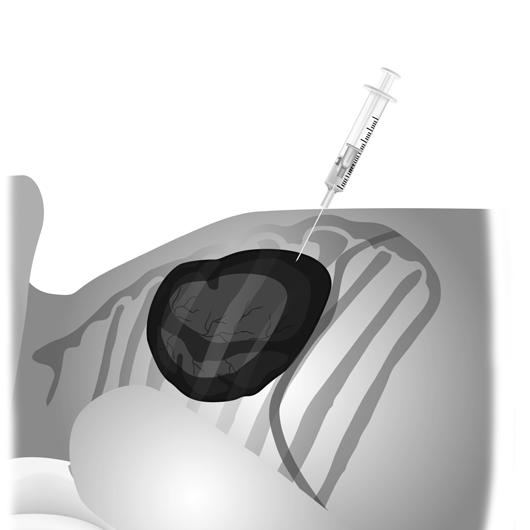

7. Com o abocath, avançar até que uma diminuição da resistência é sentida; em seguida, retira-se o mandril e aspira-se. Com a agulha, avança-se lentamente em aspiração negativa ligeira, até drenagem de ar ou líquido.

8. Usar a terceira via da torneira para desperdício de ar/líquido.

Adaptado de Cernadas (2005).

Figura 9.2.6 – Local de punção e inclinação da agulha. A. Face: direção da agulha alinhada à região média da clavícula esquerda; B. Perfil.